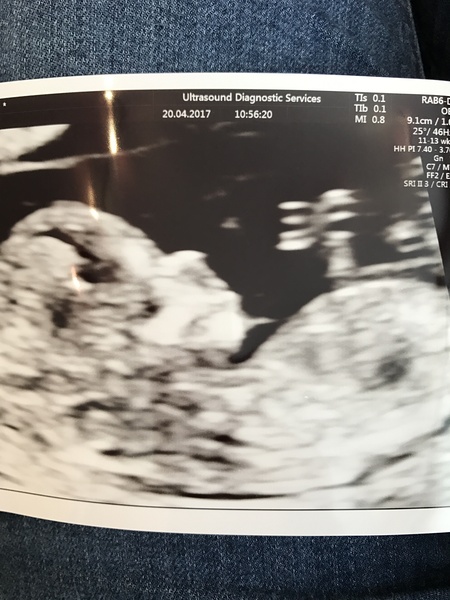

Had my dating scan today and all is well! Baby was wriggling and stretching its legs and waving its arms. I need to wait until next week for the full NT results though. They moved my EDD forward to 28th October but I'm still going to hang around on this board if you'll have me, I suspect the little one will turn up late if it takes after DH Smile

Scan was all good today

I had my booking appointment yesterday and then afterwards I had some pink, I'm a bit sore and think it could be thrush related and due to dtd but for reassurance had a scan today.

I'm bang on my dates and a heart beat was clearly seen Smile I'm 8+3

I had my booking in app yesterday and reassurance scan and I'm left confused, all looks well and there's a heartbeat but baby is only measuring 6 weeks instead of 8/9! Back in 2 weeks for another scan